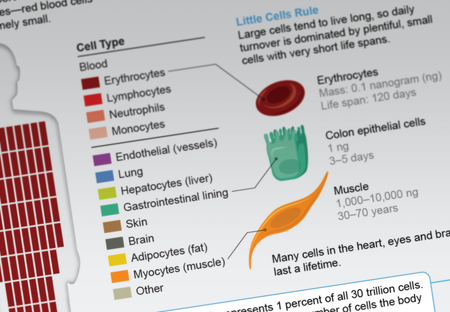

See Your Body’s Cells in Size and Number

The larger a cell type is, the rarer it is in the body—and vice versa—a new study shows

Our Bodies Replace Billions of Cells Every Day

Blood and the gut dominate cell turnover